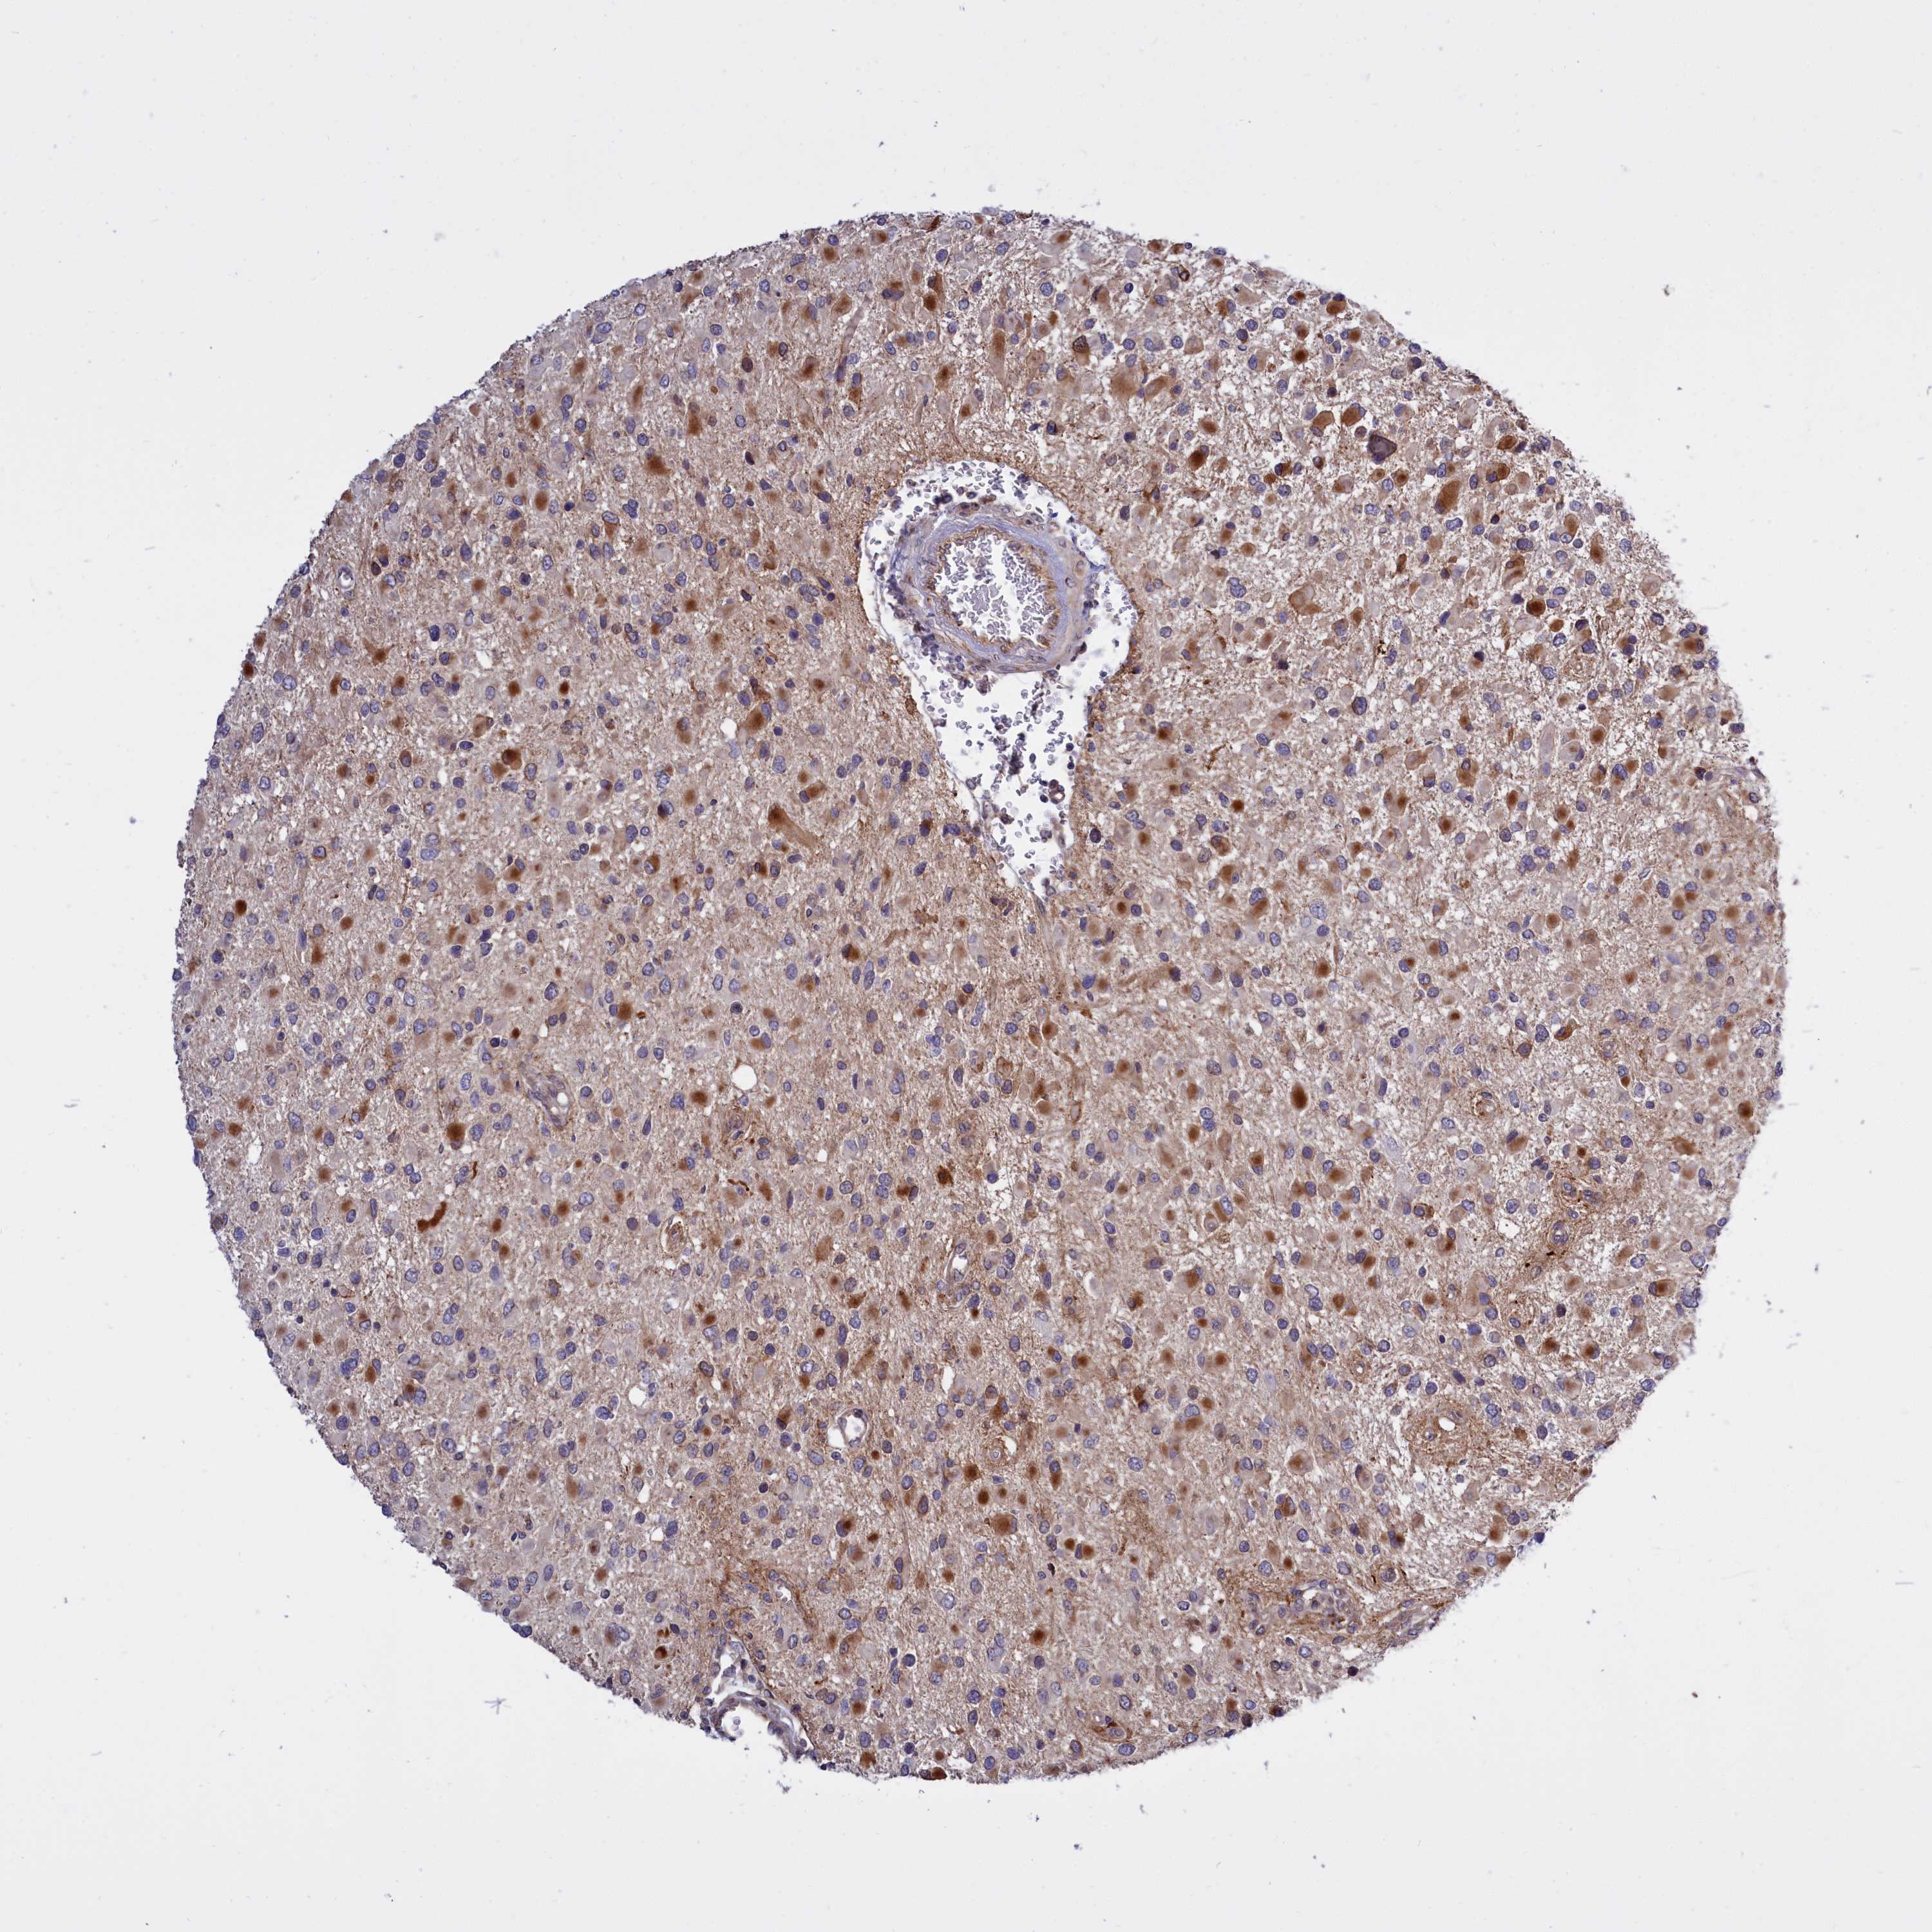

GLIOMA - Protein expressioni

A mouse-over function shows sample information and annotation data. Click on an image to view it in a full screen mode. Samples can be filtered based on level of antibody staining by selecting one or several of the following categories: high, medium, low and not detected. The assay and annotation is described here.

Note that samples used for immunohistochemistry by the Human Protein Atlas do not correspond to samples in the TCGA dataset.

Antibody stainingi

Antibody staining in the annotated cell types in the current human tissue is reported as not detected, low, medium, or high, based on conventional immunohistochemistry profiling in selected tissues. This score is based on the combination of the staining intensity and fraction of stained cells.

Each image is clickable and will lead to virtual microscopy that enables deeper exploration of all samples and also displays staining intensity scores, fraction scores and subcellular localization as well as patient and tissue information for each sample.

Antibody HPA028968

Antibody CAB004388

Staining

High

Medium

Low

Not detected

Intensity

Strong

Moderate

Weak

Negative

Quantity

>75%

75%-25%

<25%

None

Location

Nuclear

Cytoplasmic/membranous

Cytoplasmic/membranous,nuclear

Glioma, malignant, High grade

Glioma, malignant, Low grade

Glioma, malignant, NOS